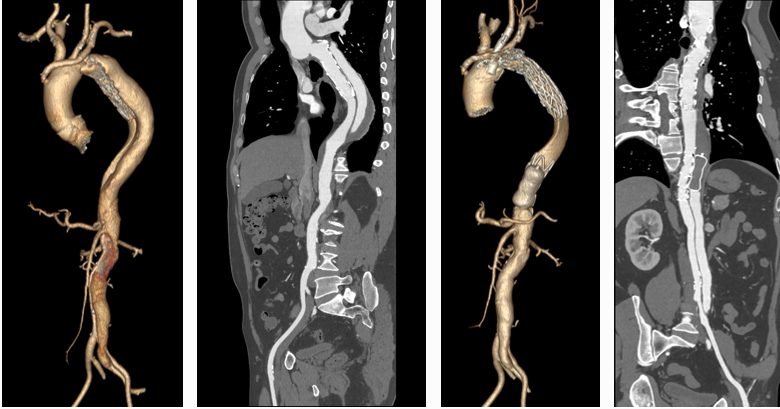

★ 301分型核心价值

分型依据:基于真/假腔与胸椎的空间关系(B1: 真腔贴椎体;B2: 螺旋混合;B3: 假腔贴椎体)

预后关联:

① B3型24个月胸主动脉扩张风险最高(42%,HR=13.91 vs B1型参照)

② B1型预后最佳(97%免于扩张)

意义:为TEVAR术后风险分层提供新工具(Mayo Clin Proc. 2020)